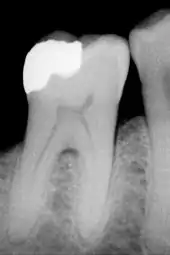

Cela consiste essentiellement à éliminer les tissus cariés et à remplacer les tissus manquant par une obturation coronaire.

- La technique directe, consiste à placer un matériau en phase plastique (c’est-à-dire mou) dans la cavité résiduelle et de l'y faire durcir. Les matériaux que l'on peut utiliser sont : les amalgames, les résines composites, les verres ionomères ainsi que de nombreux matériaux hybrides mélange des précédents. Cette technique a comme avantage d'être rapide, simple et peu onéreuse. En revanche elle est peu pérenne du fait que l'interface entre le matériau et la dent (appelé le joint) est large.

- La technique indirecte consiste à prendre l'empreinte de la cavité que l'on veut obturer, le prothésiste fabrique ensuite la pièce juste manquante. Les matériaux pouvant être utilisés sont : les métaux et alliages métalliques (or, nickel-chrome, chrome-cobalt), la résine cuite, la céramique (ou porcelaine). La pièce issue de cette technique s'appelle un inlay. Quand la cavité est très grosse et que des parties entières de dents sont à reconstruire, on les appelle onlay. Cette technique a comme avantage d'être très pérenne, très satisfaisante esthétiquement (sauf quand le matériau utilisé est métallique), mais extrêmement onéreuse (de 10 à 20 fois le prix d'une restauration par technique directe).